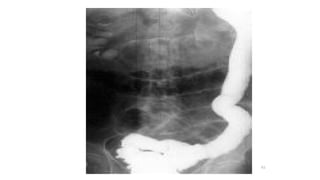

Abdominal radiographs

• 2 views are required which are Supine and Erect

• Small bowel lie centrally and colon peripherally

Abdominal radiographs cont..

• Jejunal obstruction shows valvulae conniventes i.e. parallel lines

spanning the entire width of the bowel lumen

• Obstructed ileum appears cylindrical with less clearly valvulae

conniventes

• Obstructed colon shows dilated bowel with haustral markings

59